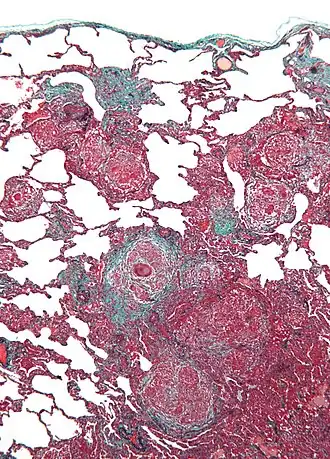

Гиперчувствительный пневмонит, ранее экзогенный аллергический альвеолит, обусловлен реакциями иммунной системы на внешние (экзогенные) антигены, возможно протекание заболевания не по аллергическому типу гиперчувствительности, а также как аллергия: острая форма протекает по III типу, подострая и хроническая формы по IV типу[3]. Распространённость этого вида альвеолита быстро растёт.

Этиология

Аллергенами, вызывающими данный тип болезни является органическая пыль, которой могут быть споры грибков, которые находятся в прелом сене, кленовой коре; реже — растительная пыль, белковые антигены, домашняя пыль, лекарственные средства. Они поступают в организм с вдыхаемым воздухом или (реже) неингаляционным путём. Как и при идиопатическом фиброзирующем альвеолите, при экзогенном альвеолите основную роль в патогенезе играет иммунокомплексный механизм повреждения тканей.[4] Комплексы антиген-антитело откладываются в стенках альвеол, мельчайших бронхиол и кровеносных капилляров, вызывая их воспаление с исходом в фиброз, возможно образование гранулём.

ЭАА может протекать в острой, подострой и хронической формах, что зависит от частоты и длительности контакта организма с антигеном, дозы антигена и общей реактивности иммунной системы. Симптомы болезни напоминают симптомы ИФА, но с обильным выделением мокроты; могут быть другие аллергические симптомы — миалгия, сыпи, головная боль. Возможен приступ бронхиальной астмы. При остром течении возможны выраженная потливость, лихорадка, потеря аппетита, похудение. В постановке диагноза решающее значение имеют аллергические диагностические пробы и серологические исследования.

При острых и подострых формах ЭАА наиболее частыми находками являются снижение прозрачности лёгочных полей по типу «матового стекла», распространённые узелково-сетчатые затемнения (до 3 мм во всех участках лёгких). Рентгенологические изменения при остром течении ЭАА обычно разрешаются в течение 4-6 нед при отсутствии повторного контакта с причинным АГ. Для подострой и хронической форм характерны множественные мелкоочаговые тени на фоне сетчатой перестройки лёгочного рисунка. Возможно формирование сотового лёгкого. При компьютерной томографии можно выявить диффузное повышение плотности ткани лёгких, утолщение стенки сегментарных бронхов, множественные мелкоочаговые тени на фоне сетчатой перестройки лёгочного рисунка..